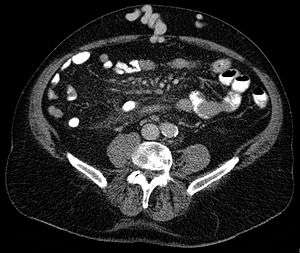

Axial CT showing portosystemic collateral circulation via the umbilical vein: caput medusae in liver cirrhosis | |

Caput medusae, also known as palm tree sign, is the appearance of distended and engorged superficial epigastric veins, which are seen radiating from the umbilicus across the abdomen. The name caput medusae (Latin for "head of Medusa") originates from the apparent similarity to Medusa's head, which had venomous snakes in place of hair. It is also a symptom of portal hypertension. It is caused by dilation of the paraumbilical veins, which carries oxygenated blood from mother to fetus in utero and normally closes within one week of birth, becoming re-canalised due to portal hypertension caused by liver failure.